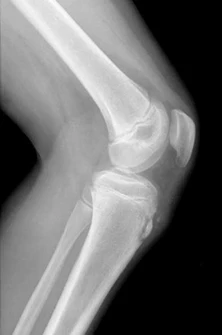

An 8 year-old boy fell out of a swing landing on his extended left elbow. The radiologist has read the x-ray as negative but upon further review the image shows this radiographic sign that is concerning for an occult supracondylar humerus fracture.

What is a fat pad sign (posterior fat pad and anterior sail sign)?